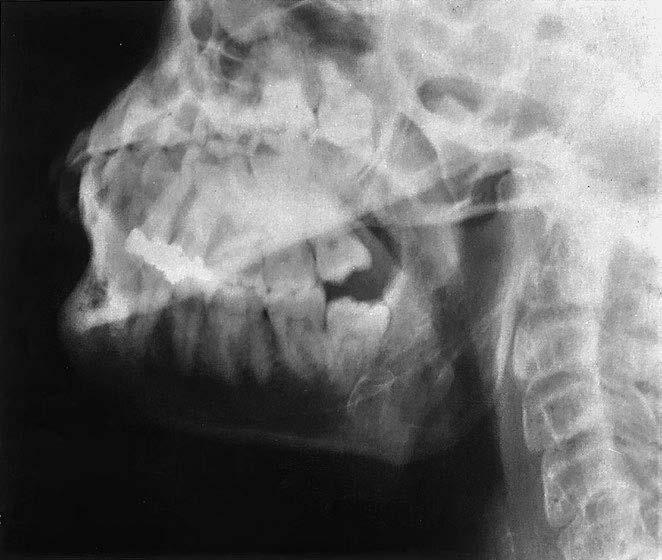

1 processus styloideus (bodcovitý výběžek)

2 palatum molle (měkké patro)

3 caput mandibulae (hlavice dolní čelisti)

4 processus condylaris 5 arcus zygomaticus (jařmový oblouk)

6 processus coronoideus (krkavčitý výběžek)

7 dno orbity (očnice)

8 cavitas nasi (nosní dutina)

9 palatum durum (tvrdé patro)